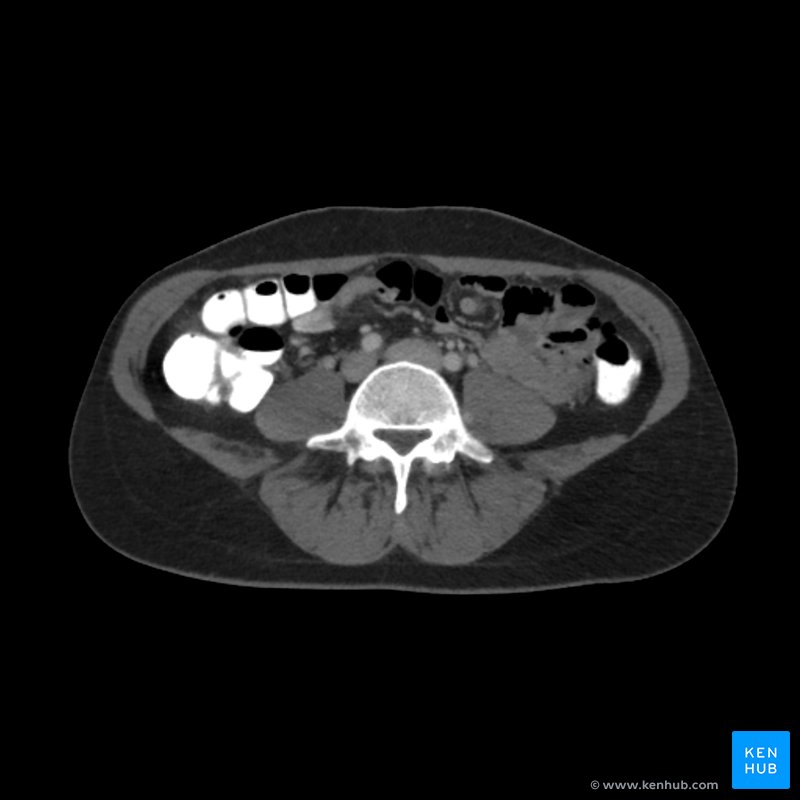

From www.kenhub.com

Abdominal CT How to read the abdominal CT Kenhub Ct Scan Of Stomach Ultrasound is the best test for this. Ct scanning of the abdomen may not see gallstones well. A ct scan is a medical imaging tool that allows doctors to see inside the abdomen and pelvic area. Healthcare providers use abdominal computed tomography (ct) scans to diagnose various diseases and conditions, including cancer, blood clots, kidney or bladder stones, ulcerative colitis,. Ct Scan Of Stomach.